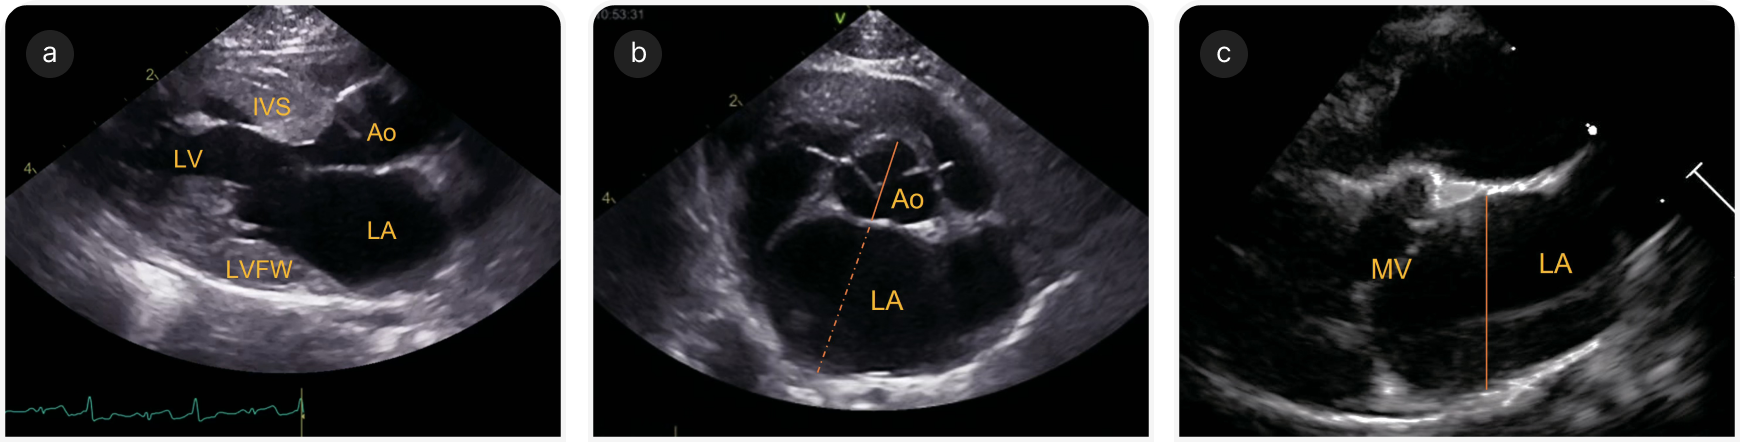

Необходимо с помощью двухмерной эхокардиографии в правой парастернальной проекции в конце диастолы (момент до закрытия створок митрального клапана) оценить состояние межжелудочковой перегородки и свободной стенки ЛЖ (Рисунок 4a).

2. Размер левого предсердия

Размер ЛП является независимым фактором риска ЗСН, ТЭ и сердечной смерти, и его можно оценить в правой парастернальной проекции по длинной и по короткой оси. В проекциях по короткой оси на уровне основания сердца измерения проводят в ранней диастоле (кадр после закрытия створок аортального клапана), при этом диаметр предсердия индексируют по аорте (LA/Ao; Рисунок 4b). Аорту измеряют от средней точки выпуклой кривизны стенки правого коронарного синуса аорты до точки слияния стенки аорты с некоронарным и левым коронарным синусами аорты. Размер ЛП определяют от этой последней точки до свободной стенки ЛП, избегая входа в легочную вену (17).

В парастернальной четырехкамерной проекции cправа по длинной оси следует оптимизировать изображение ЛП и измерить диаметр левого предсердия (LAD) в конце систолы (момент, предшествующий открытию створок митрального клапана), проведя линию параллельно митральному кольцу от межпредсердной перегородки до свободной стенки ЛП (Рисунок 4c) (18). LA/Ao >1,6 и LAD >16,0 мм соответствуют расширению ЛП; LA/Ao >1,8–2,0 или LAD >18–19 мм считают признаком умеренного или тяжелого расширения ЛП. Также для оценки систолической функции можно определить фракционное укорочение ЛП. Для оценки риска развития ЗСН и ТЭ также важны субъективная оценка размера ушка левого предсердия, наличие спонтанного эхоконтрастирования или тромба, а также оценка скорости движения ушка левого предсердия.